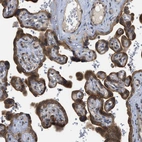

Immunohistochemistry analysis in human parathyroid gland and liver tissues using HPA015737 antibody. Corresponding EIF2AK3 RNA-seq data are presented for the same tissues.